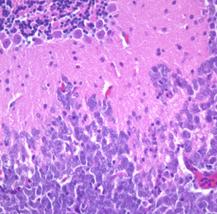

Human medulloblastoma  tumor cells (blue cells at bottom) growing in a mouse brain (pink areas)

The problem: most of the drugs we use to treat medulloblastoma are 30 years old. In the past 5 years we have learned a lot in the laboratory about different subtypes of medulloblastoma (there are at least 4 - and probably 6 - subtypes). But while we have learned more about what makes these cancer cells grow, we are lacking new therapies that we can use to kill cancer cells. In particular, we need drugs that will work on the worst prognosis subtypes.

Our goal: To develop new, less toxic therapies for patients with aggressive medulloblastoma. We set out to find drugs that would kill cells that had activation of a gene called MYC. The two worst subtypes of medulloblastoma have high levels of this gene, indicating they may be sensitive to drugs that target MYC.

Our progress: Targeting the “Achilles’ Heels” of MYC-driven medulloblastoma. One of the ways that MYC makes cancer cells grow more is by changing their metabolism. This may also represent an Achilles’ heel for these cancers. There are drugs that specifically target the metabolic changes downstream of MYC. The good news is that these drugs don’t appear to harm the normal brain or even baby brain cells. Some of these drugs were tried years ago in children in clinical trials, but they were never extensively tested in MYC-driven cancers. We have found that these drugs not only kill medulloblastoma cells in a dish, but that they can cause regression of advanced medulloblastoma tumors growing in mice. With a little more pre-clinical testing, we hope to move this drug into clinical trials for children with MYC-expressing medulloblastoma.